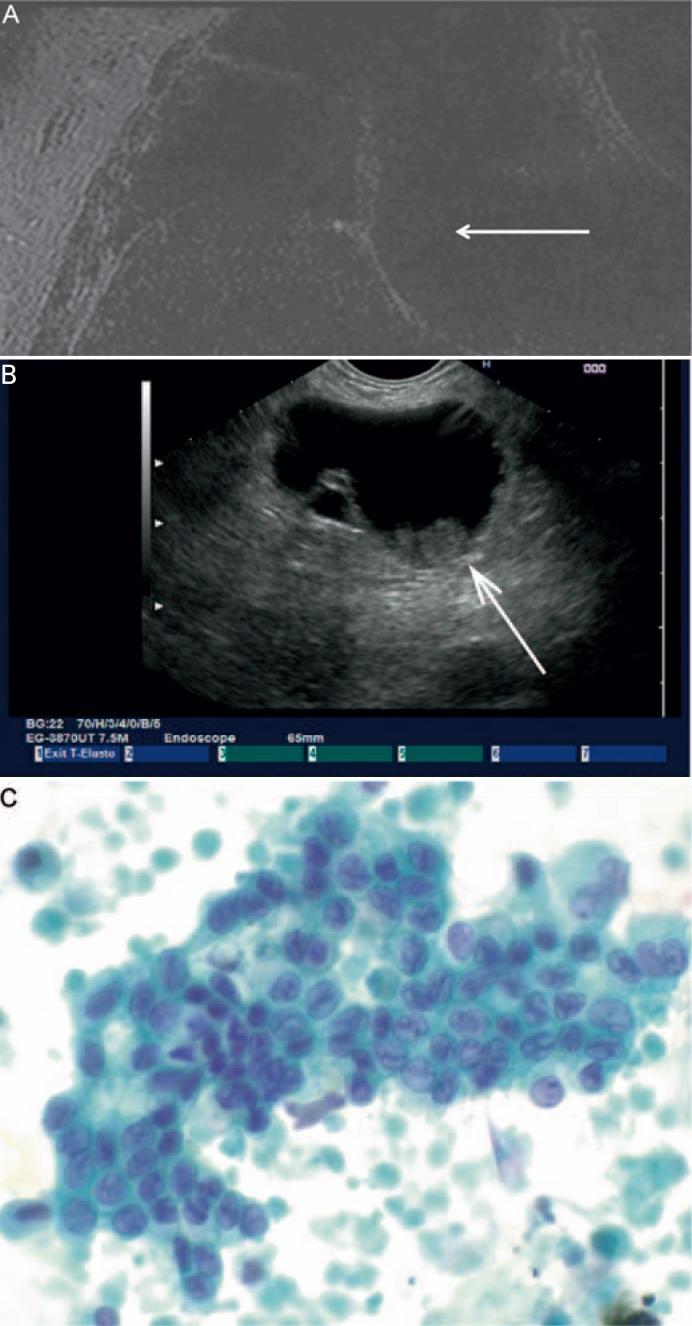

Cyst Features and Risk of Malignancy in Intraductal Papillary Mucinous Neoplasms of the Pancreas: Imaging and Pathology.

Intraductal papillary mucinous neoplasms (IPMNs) display diverse macroscopic, histological, and immunohistochemical characteristics with typical morphological appearance in magnetic resonance imaging. Depending on those, IPMNs may show progression into invasive carcinomas with variable frequency. Overall, IPMN-associated invasive carcinomas are found in about 30% of all IPMNs, revealing phenotpyes comparable with conventional ductal adenocarcinomas or mucinous (colloid) carcinomas of the pancreas. In Sendai-negative side-branch IPMNs, however, the annual risk of the development of invasive cancer is 2%; thus, risk stratification with regard to imaging and preoperative biomarkers and cytology is mandatory.

The present study addresses the radiological and interventional preoperative measures including histological features to determine the risk of malignancy and the prognosis of IPMNs.

While preoperative imaging largely relies on the detection of macroscopic features of IPMNs, which are associated with a divergent risk of malignant behavior, in resected specimens the determination of the grade of dysplasia and the detection of an invasive component are the most important features to estimate the prognosis of IPMNs.